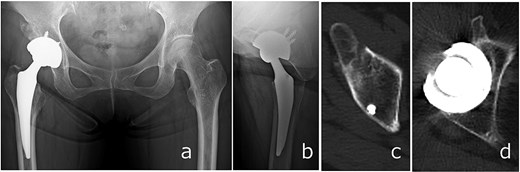

Full weight-bearing was allowed from postoperative day 1. The patient regained independent ambulation and was discharged home on postoperative day 28. At 6 months, she had resumed recreational activities with a Harris Hip Score of 92. No complications were observed, and follow-up CT demonstrated healing of the anterior wall fracture and partial union of the AIIS fragment (Fig. 5).

Radiographs (a and b) and CT images (c and d) obtained at 6 months postoperatively, showing stable implant fixation and partial union of the anterior inferior iliac spine and acetabular anterior wall fractures.